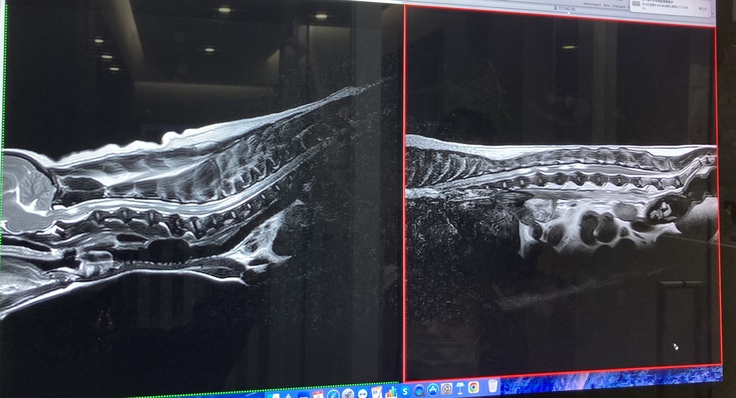

今年に入ってからは痙攣が始まり3月に地元の動物病院にてMRI検査を受けました。診断は、脊髄空洞症で、痙攣はその痛みからくる症状と言われました。

しかし、今年4月東京へ渡航し、動物医療センター(循環器科・脳神経科)での専門的な検査(CT・MRI)を2日間に渡り行った結果、MRI検査では「脊髄空洞症」と「てんかん」両方あること、その他にも多発性ヘルニア(腰椎、頚椎、他)が発覚し、痙攣の方はてんかんによるものと診断を受けました。 胆泥症・てんかん・脊髄空洞症に関してはこれ以上悪くならないように定期的な検診や毎月の通院、一生涯毎日の薬剤投与となりました。